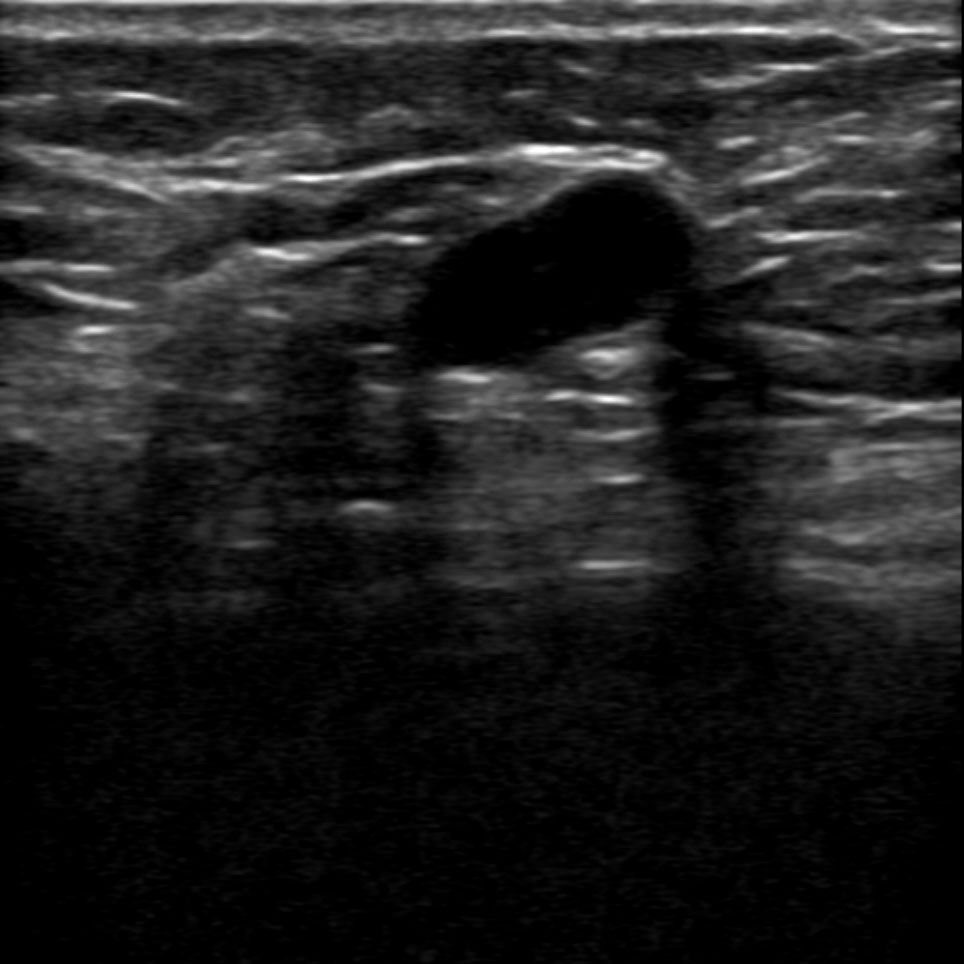

原始的超声图像像天书一样,除了专业超声医生谁都看不懂,新名医率先实现了针对超声实时动态图像的特定目标、多目标识别,准确率超过93%,超声AI数据集规模、识别准确率、移动端工程实现能力业内领先。

传统超声的多普勒测量非常繁琐,需要设置大量参数手工操作,新名医全球首创一键多普勒测量,AI自动找到血管、自动计算出12项血流动力学参数,让复杂的超声变得像血压计一样,读数就可知道异常,提示粥样动脉硬化、血管狭窄、易损斑块、流速异常等多种脑梗风险。

智能手持超声提供覆盖全身的优异图像